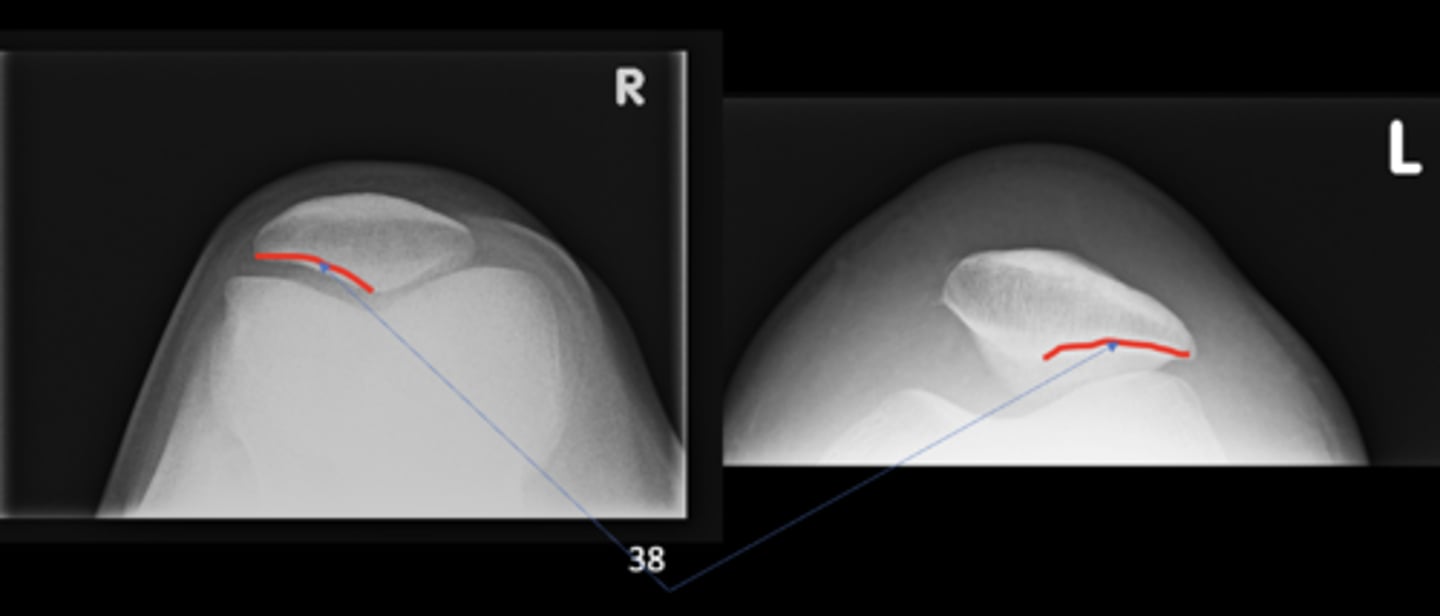

14

New cards

- Femoral head

Lateral patellofemoral joint

ID 38 (joint)